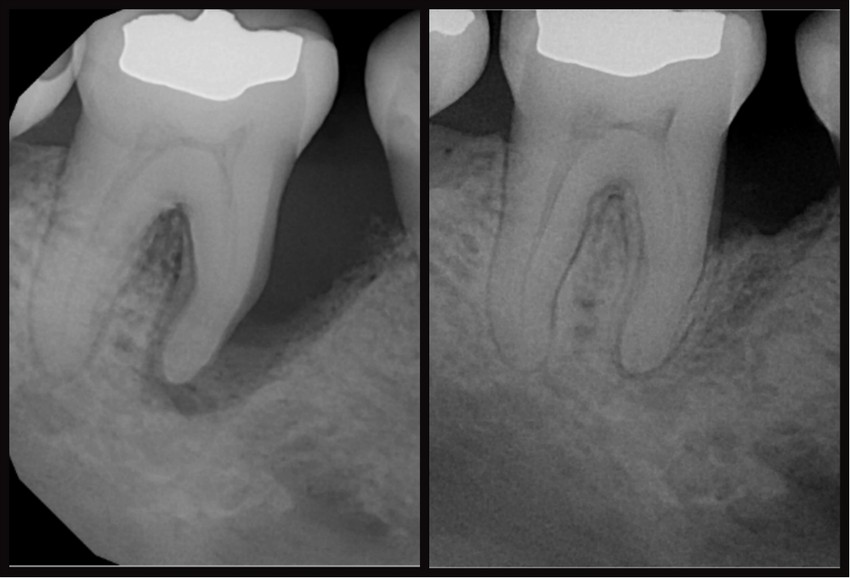

Aggresszív fogágybetegség klinikai ésröntgenképe